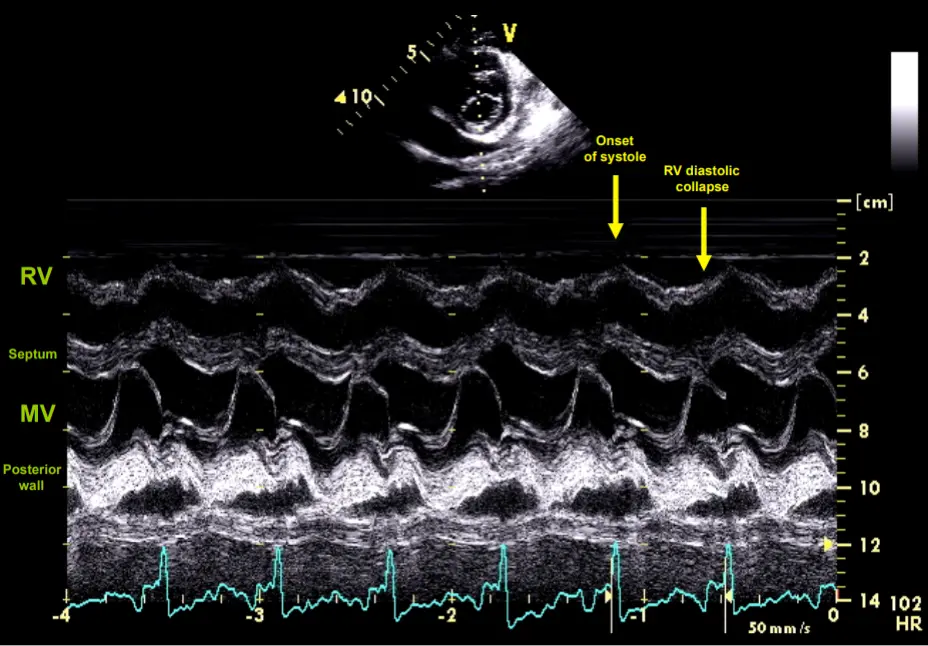

Late Echo Findings

- Early diastolic collapse of RV

- Late diastolic collapse of RA